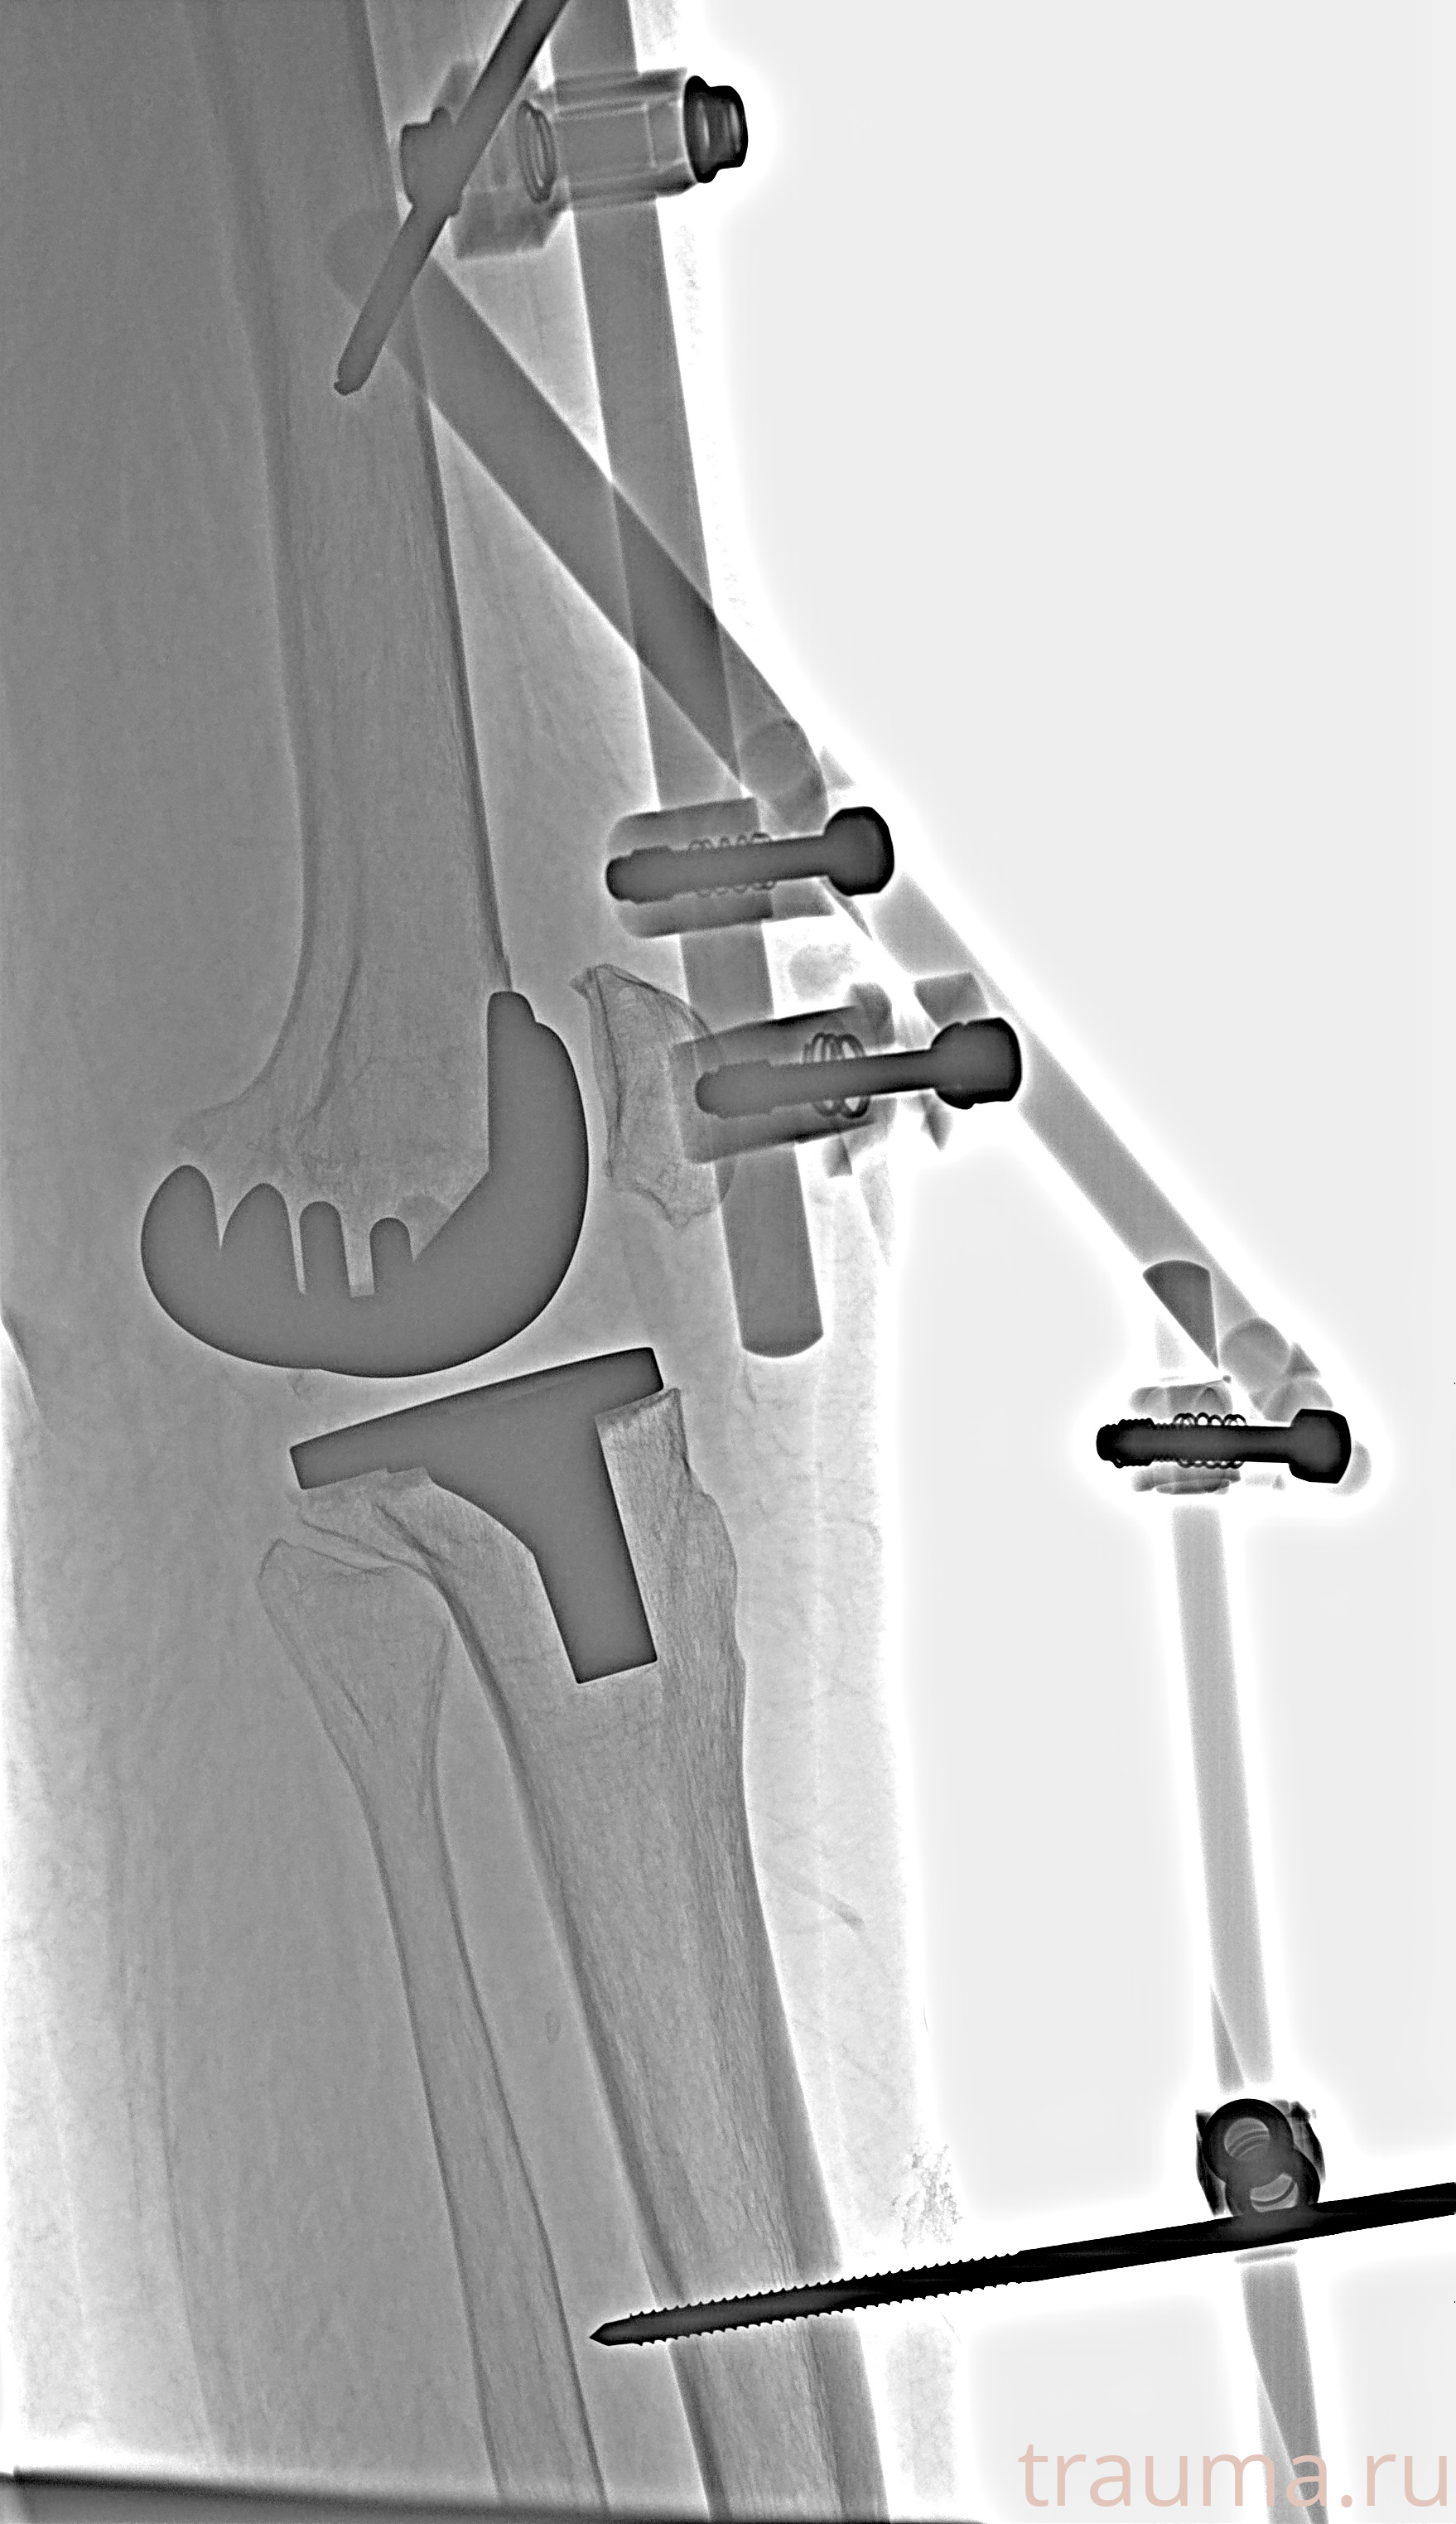

Рентгенограммы

Рентген на дому: по вашему адресу приезжает врач-рентгенолог, травматолог-ортопед с мобильным рентгеновским аппаратом, проводит диагностику травмы или заболевания, делает необходимые рентгенограммы, дает рекомендации по дальнейшему лечению. Получить качественные снимки в домашних условиях возможно благодаря уникальной методике, разработанной МосРентген Центром для института  Склифосовского